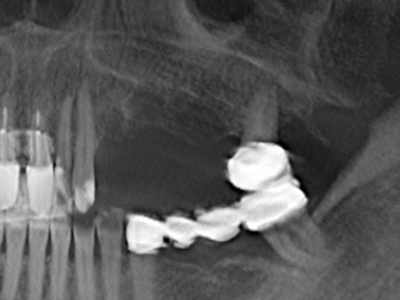

Sollen chirurgische Eingriffe mit unmittelbarer Knochenbeziehung an empfindlichen Strukturen wie Blutgefäßen oder Nerven erfolgen, so bergen rotierende Instrumente ein erhebliches Potential an iatrogener Schädigung. Gerade bei Nervdarstellungen nach iatrogener Schädigung, oder aber im Zuge einer Nervlateralisation für resektive und rekonstruktive Eingriffe oder Implantatinsertionen können piezoelektronische Geräte hilfreich sein Knochendeckel zu präparieren und nervnahe Hartgewebsanteile zu entfernen (Abb. 17-20). Ein leichter Kontakt des Nervstrangs zur Piezospitze bleibt dabei in der Regel folgenlos – allerdings kann eine unvorsichtige Vorgehensweise mit sägeartigen Bewegungen bzw. Ansätzen bei noch vorhandener knöcherner Unterlage durchaus temporäre oder aber auch permanente Nervschädigungen verursachen. Das Risiko einer solchen Schädigung wird jedoch als wesentliche geringer eingeschätzt als unter Anwendung von Säge- oder Fräsinstrumenten (Pereira, Gealh et al. 2014).